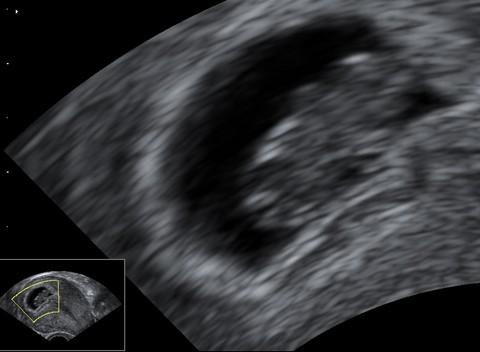

Plod stáří 8 týdnů a 6 dní, velikosti 23 mm.